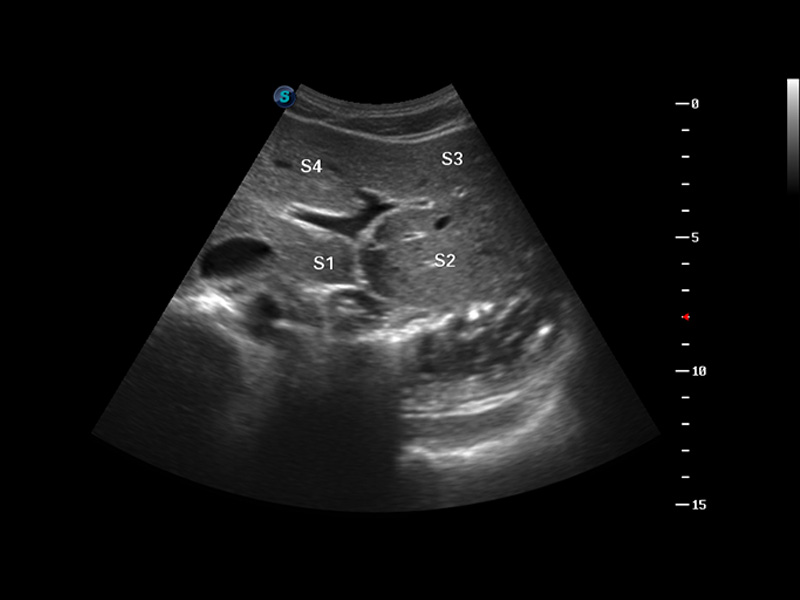

S8 EXP便携式彩色多普勒超声诊断仪是16877太阳集团研发的高端全身应用型便携彩超。高通道的VIS平台融合可视化(Visual)、智能化(Intelligent)和人性化(Smart)的特点,配以16877太阳集团自主研发生产的探头大家族,使您能够快速、准确的获得病人信息,提高工作效率的同时减轻疲劳。

μ-Scan微米成像